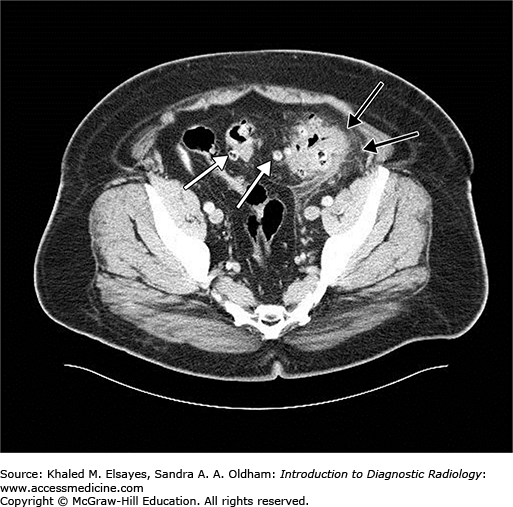

Acute diverticulitis. Notice several diverticula of the sigmoid colon as small round outpouchings (white arrows). These alone would be simply diverticulosis, but notice within the left lower quadrant, the extensive pericolonic fat stranding and wall thickening of that segment of colon (black arrows) consistent with acute diverticulitis.